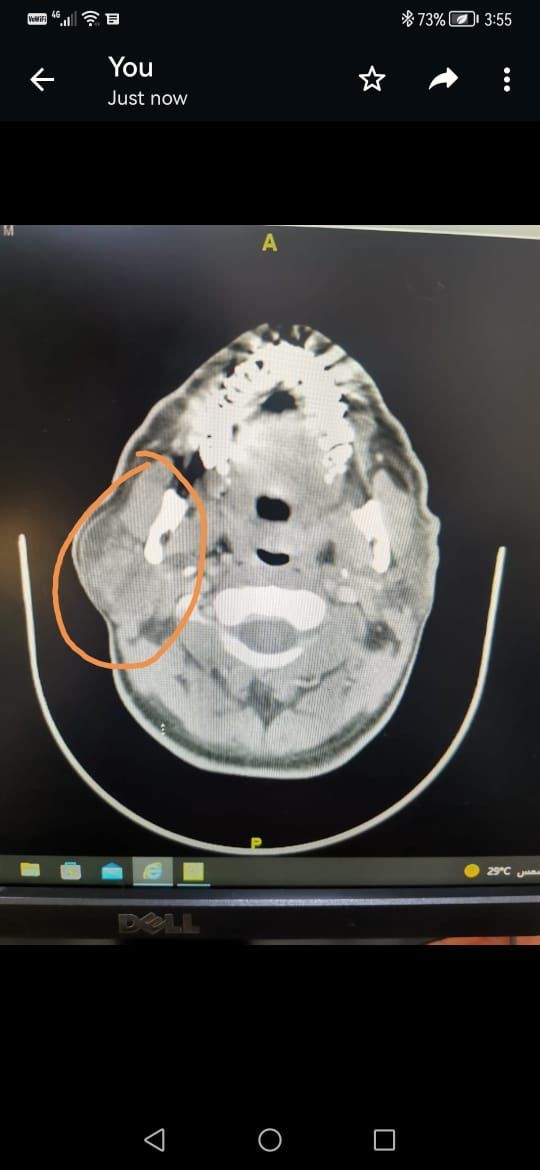

تمكن فريق من الجراحين بمجمع الملك فيصل الطبي بالطائف من استئصال ورم حميد في الغدة النكافية اليمنى لمريض خمسيني، حيث تمت معاينة المريض من قِبل فريق طبي من الاستشاريين المتخصّصين بقيادة الدكتور شكيل احمد والدكتور عادل سليمان والدكتورة آسر والدكتور سرفراس رسيل والدكتور صالح الزهراني، وتبيّن أنه يعاني من ورم حميد، وبعد إجراء الفحوص المعملية والإشعاعية المناسبة تقرّرت الخطة الجراحية المتقدمة والتي تحتاج الى إجراء جراحي للغدة النكافية، وقد استغرقت العملية ثلاث ساعات وتكللت ولله الحمد بالنجاح.

وتعد هذه العملية من العمليات النوعية بسبب ارتباط الغدة النكافية بخمسه فروع من العصب الوجهي وحيث إنها تحتاج إلى فريق طبي متخصص ذي كفاءة عالية من الجراحين والتخدير والعناية المركزة.